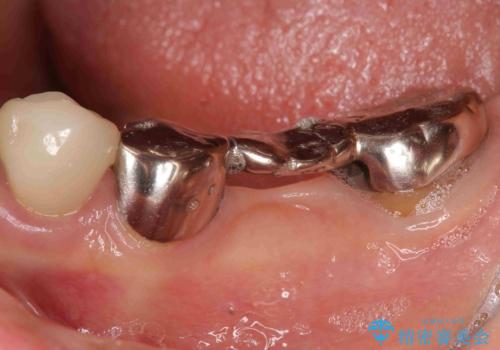

清掃しづらく、見た目の気になるブリッジ

- 毎回食事のたびに食べかすがつまり、見た目も気になる銀歯のブリッジやりかえを希望され来院されました。